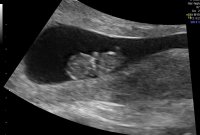

Er det noen som har tatt ultralyd rundt uke 9+6? Når jeg er 11+0 uker på vei skal jeg på familietreff, og tenker at hvis noen reagerer på mat og drikkevalg så kan vi liksågodt si det som det er. Men, da må jeg fortelle det til barna først. Og jeg vil gjerne fortelle det med et ultralyd bilde sånn at de skal kunne forholde seg til det som ekte, ikke bare en beskjed de får fra mamma.. Så.. Hvis noen har vært på ultralyd rundt uke 9+6 eller 10+0 så vil jeg gjerne se bilde

Er jo litt viktig at man ser at det er en baby der og så barna forstår hva de ser på